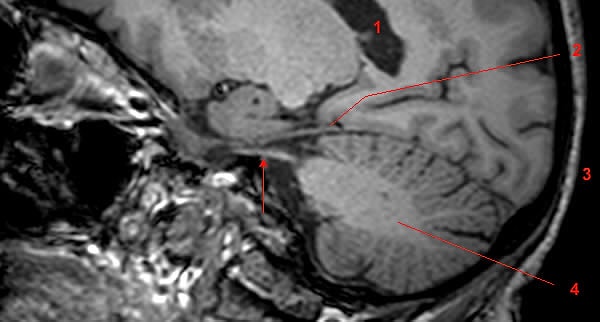

Deney kapsamında yirmi katılımcıyla çalışan Langer, fotik hapşırma refleksine sahip olan ve olmayan insanların beyinlerinin ışığa nasıl tepki verdiğini inceledi. Elde ettiği sonuçlar ise bu durumun diğer refleksler gibi yalnızca beyinsapı ve omurilikle ilgili bir tepki olmadığını, beynin diğer kortikal alanlarını da etkilediğini gösterdi.

Bu teoriye göre fotik hapşırma refleksinin sebebi burnun bir şekilde irite olmasıydı ancak tarihin iki önemli filozofunun öne sürdüğü gibi bu durumun nemle hiçbir ilişkisi yoktu. Burundaki bu rahatsızlığı yaratan, yüzümüzün duyarlılığından ve motor kontrolden sorumlu olan trigeminal sinir adı verilen beyin bölgesiydi.

Az önce sözünü ettiğimiz trigeminal sinir, beyinde optik sinirlerin yanında bulunmaktadır. Karanlık bir ortamdan güneşe çıktığımızda ve âni ve yoğun bir ışığa maruz kaldığımızda ise retinamız optik sinir aracılığıyla beyne sinyal göndererek gözbebeğimizi küçültmesi gerektiğini bildirir. Ancak bu sinyal kimi zaman optik sinirin yanında bulunan trigeminal sinir tarafından algılanabilir ve sinyaller karışarak beynimiz burnumuzun irite olduğu mesajını alabilir.